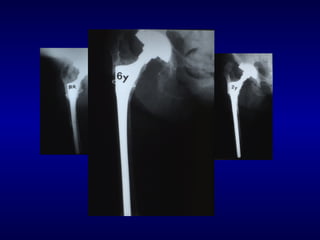

Paprosky 2B

F.U 5 aa